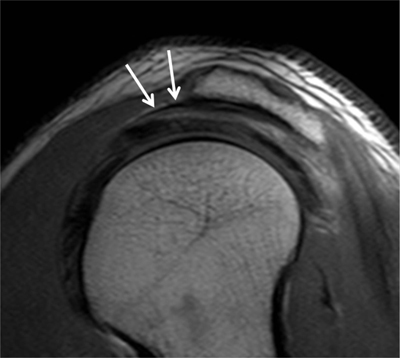

Figure 10

Subacromial pseudospur. Sagittal oblique PD-weighted MR image demonstrates the normal coracoacromial ligament at its acromial attachment that may mimic an osteophyte (arrows).

Figure 11

Subacromial pseudospur. Coronal oblique PD-weighted MR image depicts the normal attachment of the tendon of the deltoid muscle visible on one single section mimicking an enthesophyte (arrow). Analysis of consecutive coronal oblique MR images is necessary to avoid misinterpretation.